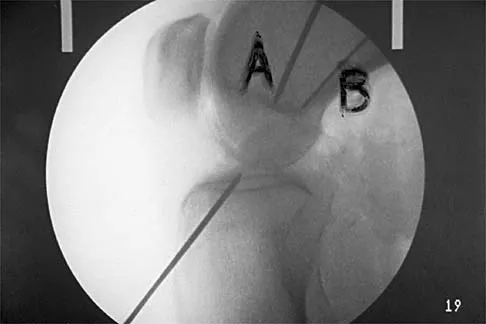

A 17-year-old girl who initially presented as a child with multiple skeletal lesions, café-au-lait spots, and precocious puberty now has bone pain. A recent bone scan reveals multiple areas of increased scintigraphic uptake, including bilateral proximal femurs. A radiograph is shown in Figure 19. Besides activity modification, what is the next best line of treatment for decreasing her pain?

Explanation

McCune-Albright syndrome is the combination of polyostotic fibrous dysplasia, café-au-lait lesions, and endocrine dysfunction. The most common endocrine presentation is precocious development of secondary sexual characteristics. Compared with bone lesions in patients without polyostotic disease, the skeletal lesions in patients with the syndrome tend to be larger, more persistent, and associated with more complications. Bisphosphonate therapy has been shown in several studies to decrease the pain associated with the skeletal lesions of fibrous dysplasia. DiCaprio MR, Enneking WF: Fibrous dysplasia: Pathophysiology, evaluation and treatment. J Bone Joint Surg Am 2005;87:1848-1864.